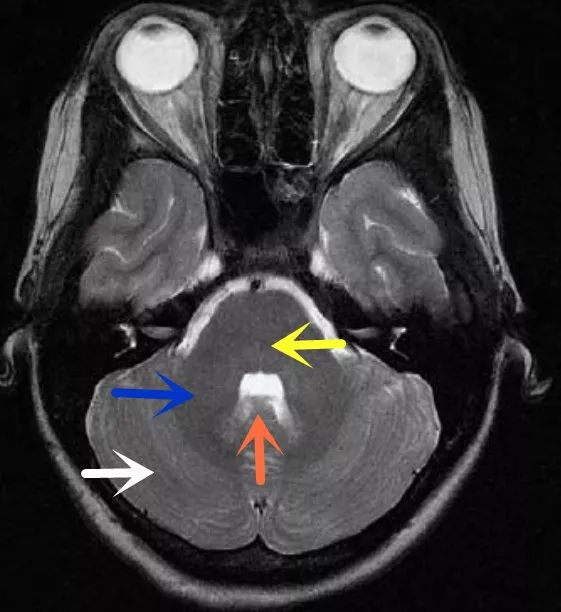

图9为所示病例同层面轴位正常T2WI图片,双侧小脑半球对称(白色箭头)、桥脑(黄色箭头)、小脑中脚(蓝色箭头)、第四脑室(棕色箭头)。后颅窝主要由枕骨和颞骨岩部后面共同组成,其内主要包含小脑半球、脑干、前庭神经等。

双侧小脑半球对称存在,与桥脑通过三对小脑脚相连(本图可见小脑中脚),前庭神经通过内听道走行,桥脑前侧为桥前池及双侧桥小脑角池,桥脑后侧、双侧小脑中脚、双侧小脑半球、小脑蚓部共同围绕第四脑室。